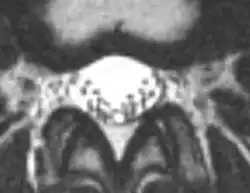

Een MRI-scan Full spine (van de volledige wervelkolom) met of zonder contrastvloeistof is een belangrijk hulpmiddel bij het stellen van de diagnose.

Voor de ossificans-vorm van de aandoening kan een niet-versterkte CT-scan de aanwezigheid en omvang van arachnoïde ossificaties aantonen. Deze is complementair aan een MRI, aangezien een MRI minder specifiek kan zijn en bevindingen kunnen worden verward met regio's van verkalking of hemosiderine.